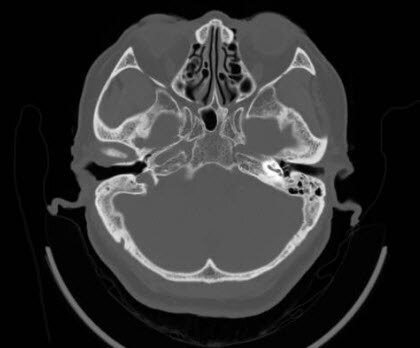

最近来自广东佛山汕头的黄女士,由于多年的鼓膜穿孔和鼓膜内陷,导致听力下降,耳鸣,非常的苦恼。一直觉得自己的鼓膜内陷了,又穿了孔,可能治不了。所以一直就拖着,几十年了,直到最近看手机,了解到佛山的耳鼻喉郑立岗医生可以做这种鼓膜内陷的耳内镜微创手术,就过来就诊了。

耳鼻喉郑立岗医生检查后确定黄女士的情况做耳内镜微创手术是没有问题的,就收住入院了。

这次做的是全麻耳内镜中耳炎微创手术,麻醉师插管全麻后就开始了手术,在耳内镜下不用做任何的体表切口,直接翻起外耳道鼓膜皮瓣,抬起内陷的鼓膜,听骨链是基本完整的,取合适大小的耳屏软骨修补鼓膜,鼓膜修补好后检查了两遍确认没问题后就结束了手术。整个的手术用时约80分钟,非常的顺利。术后查房患者无明显的不适,无手术相关的并发症。

对于鼓膜内陷伴鼓膜穿孔的中耳炎患者,耳内镜微创手术是可以解决的,这种手术的技术难度比较大,对医生的技术和经验要求非常高